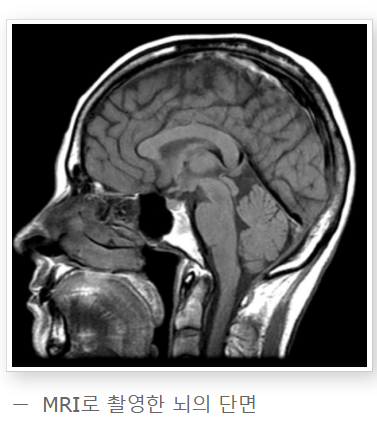

NMR의 변형 기술인 MRI(자기공명영상)는 의학적 이미징에 널리 사용됩니다.

MRI는 인체 내부 구조를 비침습적으로 촬영할 수 있어, 진단 및 치료 계획 수립에

중요한 역할을 합니다.